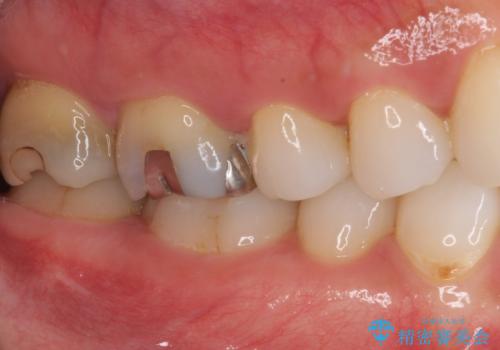

- むし歯治療途中で放置していた奥歯から、歯磨きの度に出血するとのことで来院された患者様です。

隣接する部分の間のむし歯が歯肉の奥深くにまで及んでおり、歯肉が腫れやすい状態となっていたため、歯肉の切除並びに歯槽骨の形態修正を行い、虫歯が歯肉の外に出てくるようにした上で、オールセラミックにて補綴することとしました。